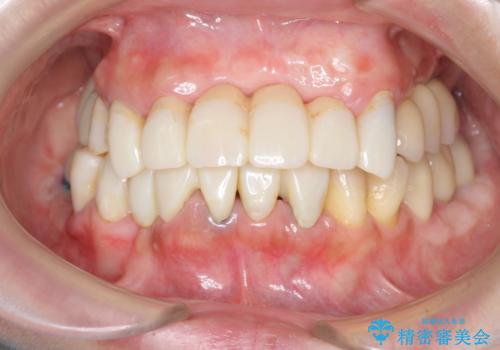

歯周病 全顎治療

- 前歯の見た目、入れ歯による噛めないことの改善を求めて来院されました。

検査により全顎的な歯周病治療、欠損のインプラント補綴、根管治療が必要な状態であることをお伝えし、治療を計画します。